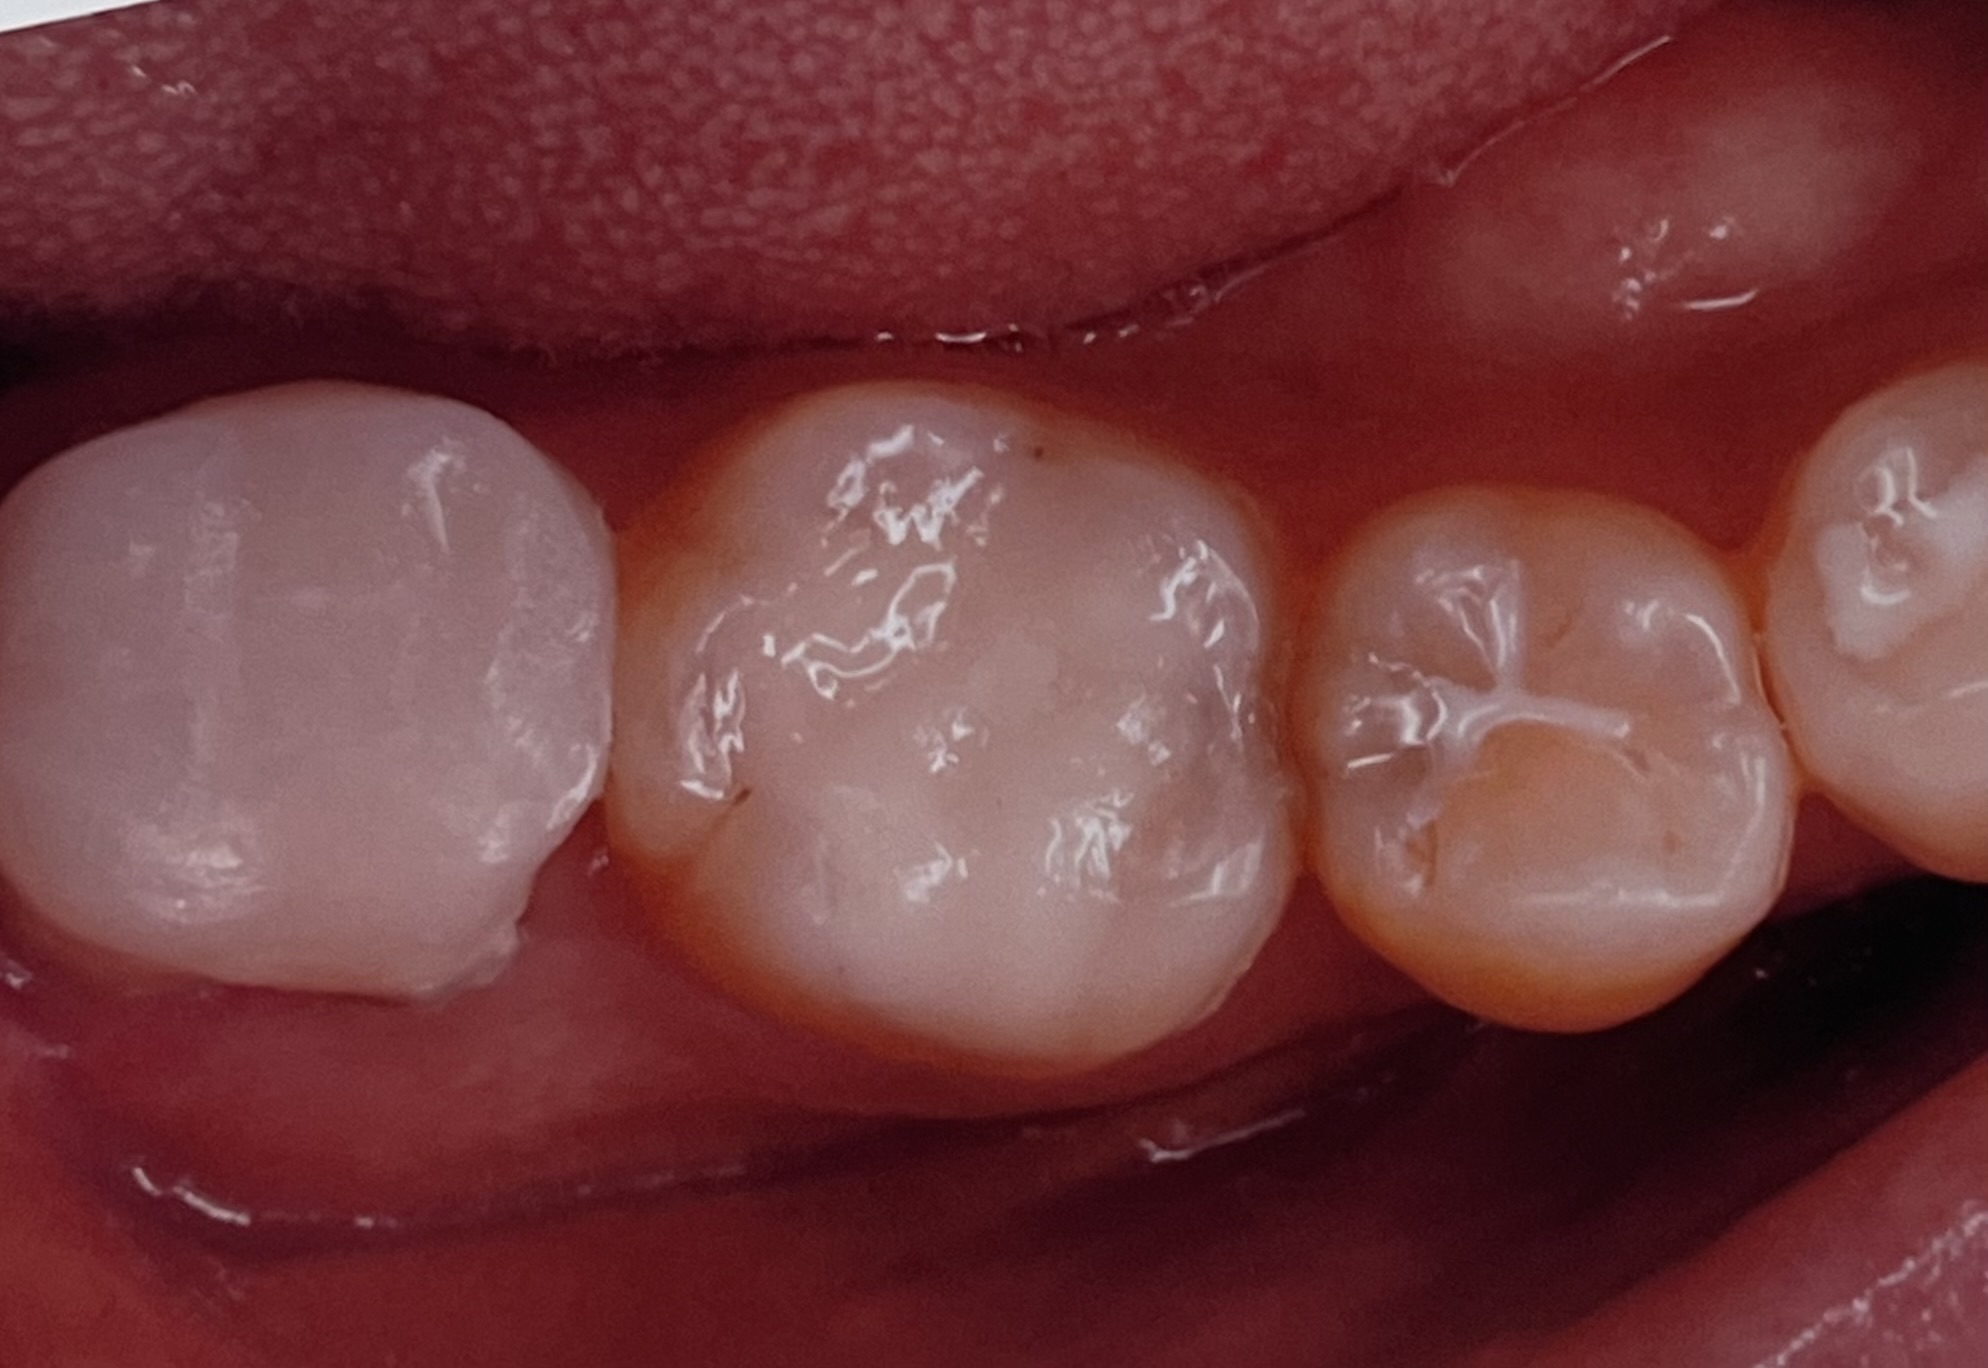

埼玉県志木市の佐藤デンタルクリニックです。今回は、部分的な銀歯を含む虫歯をぶぶんなセラミックで治療したものです。

当院での治療は、保険外にはなりますが、セレックという機械を用いて数時間で、麻酔からセラミックセットまでを行うものです、1dayトリートメントといいます、

などなど数多くあります、近頃では、セレック技術を用いての治療が10年を超えましたが、やり直しはほぼありません、(定期的なクリーニング、チェックは大切です)

ここには治療例を二つほど載せましたが、当院での治療数は、部分的なものだけで1500を超えています!そのなかで、銀歯のように外れたとかしみる、かけたなどの問題はほぼおきていません。

今回の治療は、エナミックという弾力があり、かけにくい噛みやすいセラミックを用いて行なっています、価格は、65000-80000円(税別)となります、虫歯の大きさなどによっては全体を覆うものも良いかと思いますが、歯の歯質を残したい方にはこの治療がおすすめです、